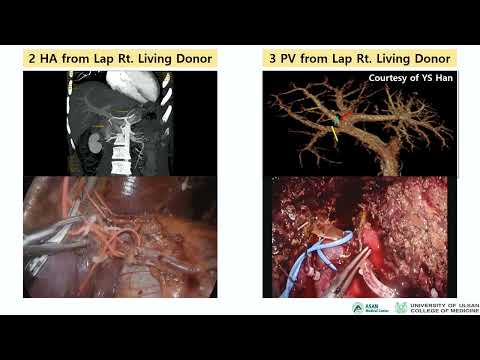

DEB16: Donor Hepatectomy Laparoscopic vs Open

Debate 16: Donor Hepatectomy Laparoscopic vs Open